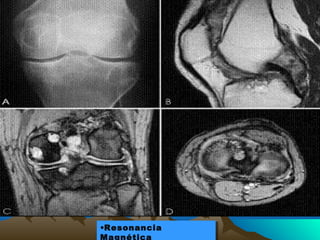

•Resonancia•Resonancia

Magnética